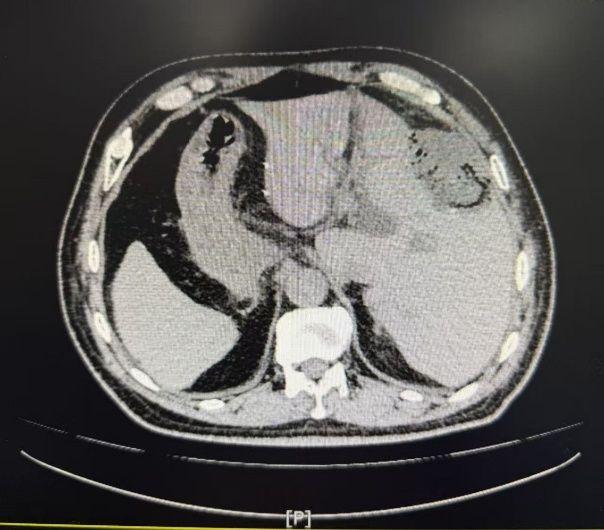

该患者为临床极少见的“镜像人”,腹腔中肝脏、脾脏、胆道及血管等位置与正常人呈镜像反位。更为棘手的是,患者曾于外院行腹腔镜胆囊切除术,首次手术造成的手术区域粘连,加之脏器反位导致的解剖结构异常,使得本次手术如同在“雷区”中穿行,分离粘连过程中极易损伤重要血管和器官,对主刀医生的经验、技巧和心理素质都是极限考验。面对前所未有的挑战,陆宏伟主任医师团队高度重视,组织了包括普通外科、影像科、麻醉科在内的多学科会诊(MDT)。团队仔细研究患者影像资料,反复推演手术入路和可能风险,制定了周详的手术预案。手术首先需要克服的难关便是安全、有序地分离腹腔内致密的粘连组织,才能暴露目标区域。手术过程中,陆宏伟主任医师精细操作,逐步还原出因反位而更为复杂的肝门部解剖结构。整个团队通力协作,逆向思维,精准辨识并保护了反位的重要脉管,最终完整切除了肿瘤侵犯的剩余胆囊床及部分肝脏组织,并完成了规范的淋巴结清扫。手术过程虽险象环生,但团队操作有条不紊,最终化险为夷,术中出血量极少。患者术后生命体征平稳,恢复良好,未出现胆漏、出血、感染等并发症,目前已顺利出院。

何为“镜像人”?“镜像人”即内脏反位(SitusInversusTotalis),是一种罕见的先天性畸形,发病率约百万分之一。指一个人的所有胸腹腔脏器位置与正常人呈镜像对称,如同照镜子一般。例如,心脏位于右侧,肝脏位于左侧,脾脏位于右侧等。绝大多数“镜像人”生理功能与常人无异,但因其解剖结构特殊,一旦患病,尤其是在需要手术时,会给诊断和治疗带来巨大挑战。